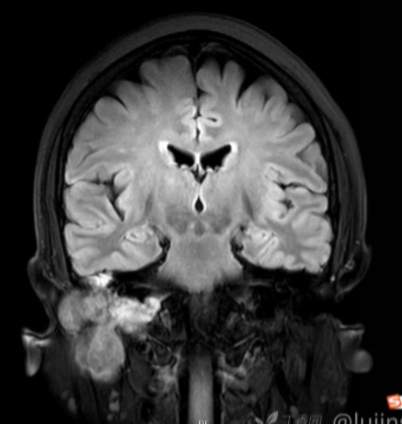

(2023-05-15 10:00,本院)行磁共振(颅脑)检查提示:右侧乳突区异常信号,考虑恶性、软骨来源肿瘤,软骨肉瘤可能性大。(集体讨论意见);脑内散在多发缺血灶。

(2023-05-12 10:15,本院)行CT(颅脑)检查提示:右侧颞骨广泛骨质破坏,伴巨大软组织肿块,性质待定,考虑肿瘤性病变,颈静脉球瘤?软骨源性肿瘤?请结合临床及病理进一步明确。

术后复查MRI: